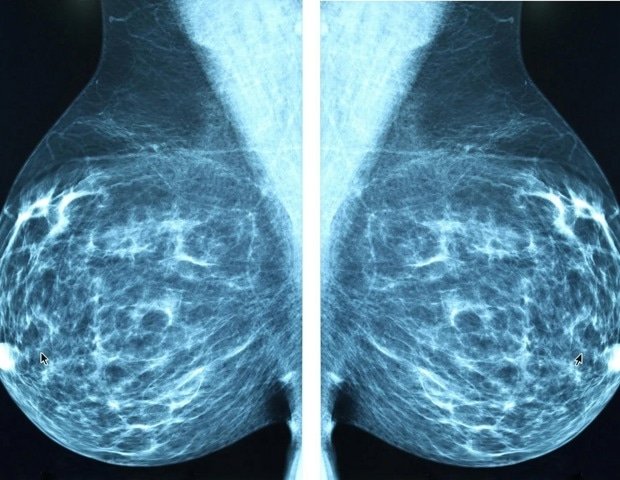

An image-only artificial intelligence (AI) model for predicting five-year breast cancer risk provided stronger and more accurate risk stratification than breast density assessment, according to a new study to be presented next week at the annual meeting of the Radiological Society of North America (RSNA).

Clairity Breast, the first image-only AI breast cancer risk model approved by the FDA, was trained on 421,499 mammograms from 27 facilities in Europe, South America and the US. The model was calibrated on an independent set of trials using a deep convolutional neural network to generate five-year hazard probabilities.

The model was applied to a study cohort of 236,422 bilateral 2D screening mammograms from five US sites and 8,810 from one European site. Mammograms were obtained between 2011 and 2017. Radiologist-reported breast density (dense vs. nondense) and five-year cancer outcomes were extracted from medical records and tumor registries, respectively. AI-predicted risks were categorized using the National Comprehensive Cancer Network thresholds: average (less than 1.7%), intermediate (1.7-3.0%), and high (greater than 3.0%).

Taking breast density into account, women in the high-risk AI group had more than four times the incidence of cancer than women in the average-risk group (5.9% vs. 1.3%). In contrast, breast density alone showed only modest segregation (3.2% for dense vs. 2.7% for nondense).